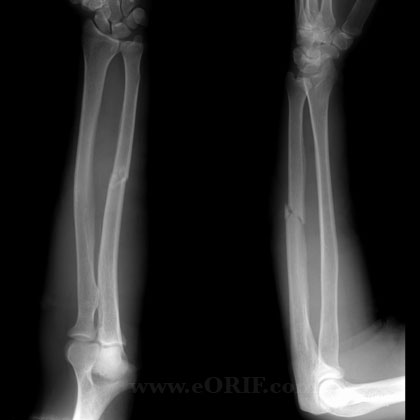

Monteggia injury

(fracture of the ulnar shaft and dislocation of the radial head at the elbow)

A _________ fracture involves fracture of the ulnar shaft and dislocation of the proximal radial head at the elbow, whilst a __________ fracture involves a fracture of the radial shaft alongside dislocation of the ulna at the distal radio-ulnar joint

A Monteggia fracture involves fracture of the ulnar shaft and dislocation of the proximal radial head at the elbow, whilst a Galeazzi fracture involves a fracture of the radial shaft alongside dislocation of the ulna at the distal radio-ulnar join